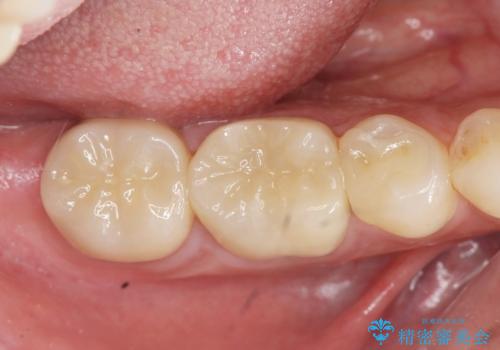

自然な仕上がりに、満足いただくことができました。

今後他の銀歯も外していく予定です。